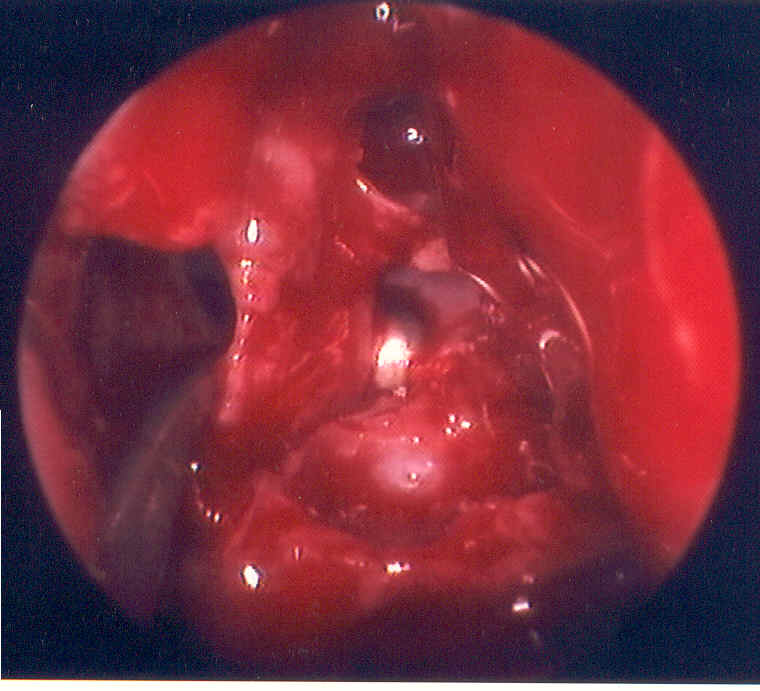

| The picture above displays the outflow tract for the ethmoid bulla. Attention to details, such as removing the bridge of tissue around this tract, leads to more rapid healing and more successful surgery | ||||||||||||||||||||